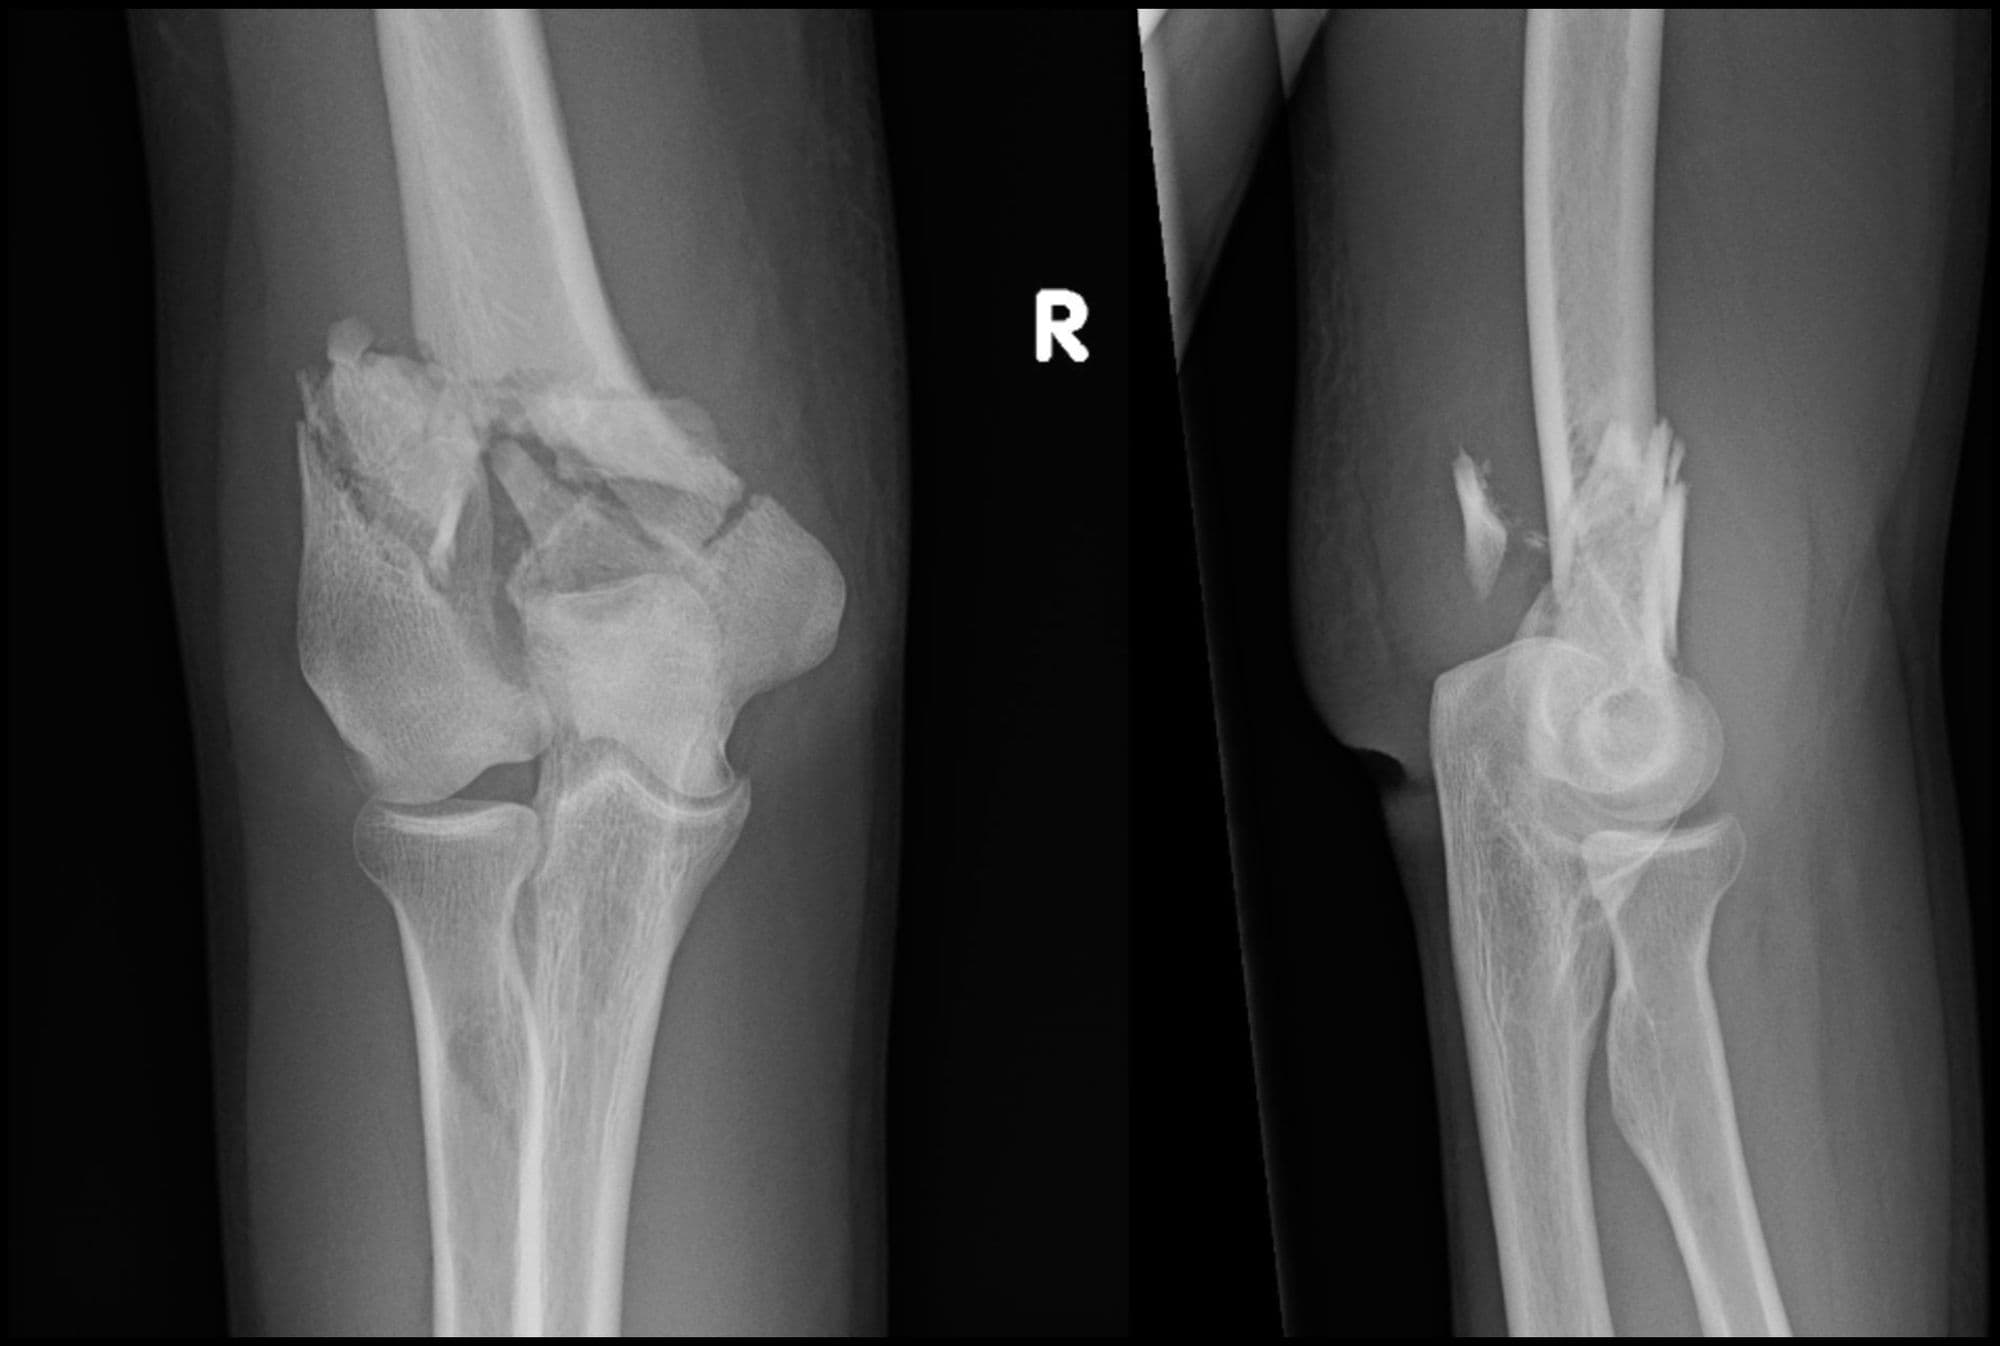

Intra-articular Distal Humerus ORIF

Christopher Lee